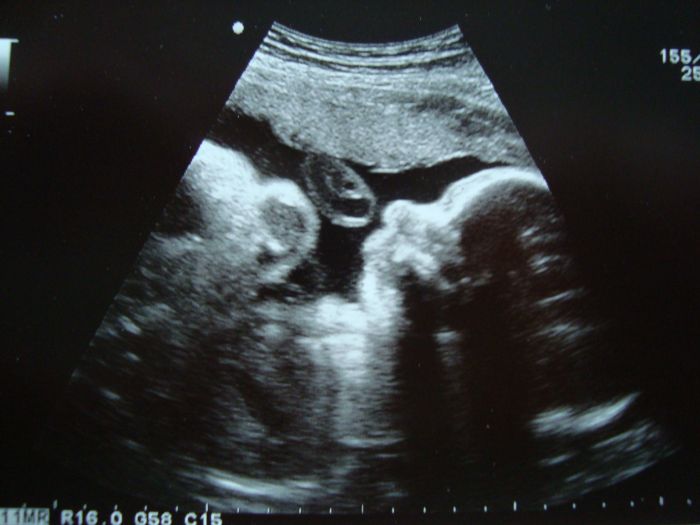

A tady fotecka z minuleho tydne 27+6. To pred pusinkou je pupecnikova klicka, nefouka bublinky :-)

[1048039] Tak takhle jsem měla přesně na svojí fotce ten pupečník, akorát ta naše na nás přímo koukala, ty to máš klasicky z profilu. Nám se pořád ukazuje zepředu a otevírá očka:-)...ale u vás prvek vypadá fakt na kluka:-)

[1048087] Me to je jasne, ze to bude kluk. :-) Tentokrat byl prvek videt i zepredu, prave nam ukazovala ty otevrene ocicka, ale fotit to moc neslo. Uz tak se snazila najit dobry uhel kvuli placente. Tak aspon mame profily a vidime, jak me meni. Od minula se fakt zakulatil. Jsem zvedava na tu pribliznou vahu. Vim, ze je to hodne zkreslene a po porodu se to muze lisit i o pul kila, ale i tak je to zajimeve vedet. No a slecny se ukazujou zepredu, jak jim to slusi, ale chlapi maji portrety vetsinou z profilu nebo pootoceni. Nevim proc, ale vybavily se mi obrazy na Konopisti. Asi mi uz fakt hrabe... :-)